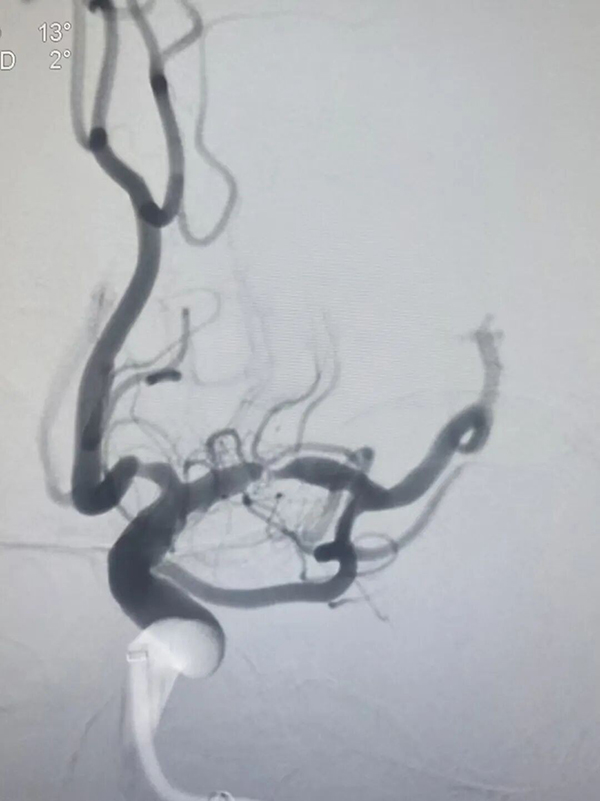

北院神经外一科副主任医师王伟君接诊后,第一时间为陈女士完善头部CT检查,结果提示“脑沟内可见血管高密度症”,病情已迫在眉睫。王伟君当机立断,先为患者实施了全脑血管造影检查。造影结果清晰显示,患者双侧大脑中动脉均存在狭窄病变,其中右侧大脑中动脉M1段重度狭窄、管腔近乎闭塞,血流淤滞严重,这正是引发急性脑梗死的“责任血管”,已达到紧急干预指征。

术中,手术团队精准操控微球囊导管,顺利穿越狭窄病变区域,缓慢充盈扩张球囊,逐步疏通闭塞血管管腔;随后精准植入支架,牢固贴合支撑血管壁,顺利疏通血管“堵点”,为脑部血流畅通搭建起稳固高效的生命通道。手术全程,医护人员全程严密监测患者生命体征与脑组织灌注状态,每一项操作均精准规范、稳妥推进。

尤为值得一提的是,手术团队在传统术式基础上创新采用“零交换”技术,一站式完成球囊预扩张、支架释放与球囊后扩张全流程操作,相较传统术式大幅减少十余次器械交替更换步骤,有效缩短透视时长、降低造影剂用量、压缩整体手术时间,在最大程度规避术中风险的同时,显著提升手术安全性与临床治疗成效。